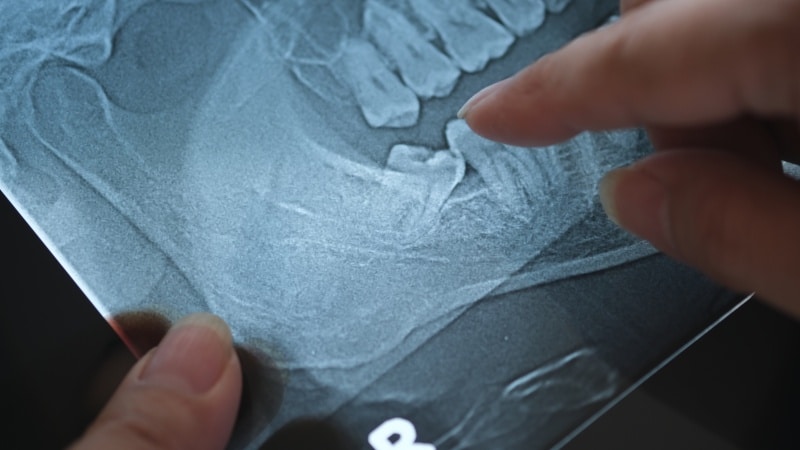

Panoramic X-ray of impacted wisdom teeth in Austin, TX

Your path to a healthier smile begins with a consultation appointment. You will meet with a board-certified oral surgeon to review X-rays and discuss your wisdom teeth removal needs. This meeting is the perfect time to ask questions about the surgery or the recovery process. The doctor will evaluate the position of your wisdom teeth to determine the best surgical approach. Getting ready for the big day involves a few practical steps at home as well: